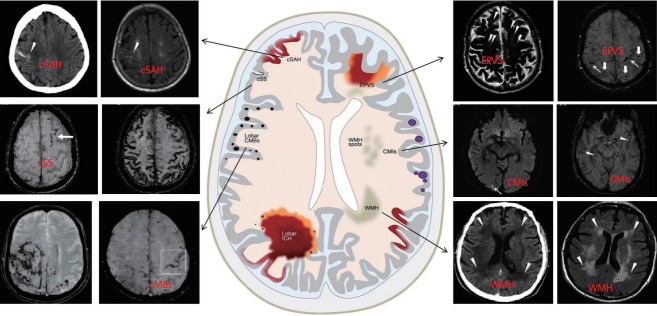

Cerebral amyloid angiopathy (CAA) has been proven to be the most common pathological change in cerebral small vessel disease except arteriosclerosis. In recent years, with the discovery of imaging technology and new imaging markers, the diagnostic rate of CAA has greatly improved. CAA plays an important role in non-hypertensive cerebral hemorrhage and cognitive decline. This review comprehensively describes the etiology, epidemiology, pathophysiological mechanisms, clinical features, imaging manifestations, imaging markers, diagnostic criteria, and treatment of CAA to facilitate its diagnosis and treatment and reduce mortality.